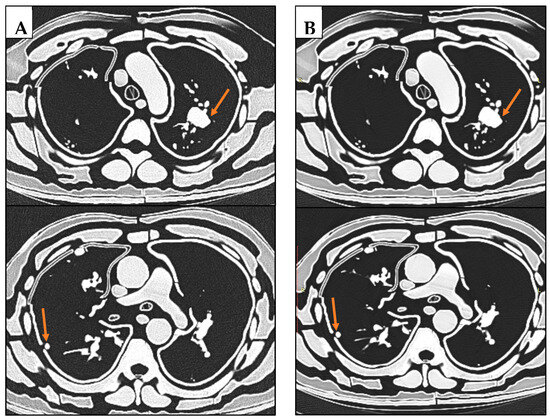

2.1. Selection of Sample Case and Image Segmentation

3.1. Radiation Equivalence